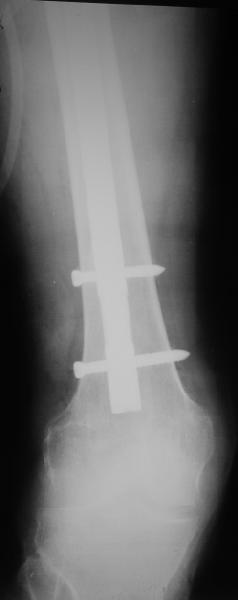

* distal fixation of the nail is based near only on two screws : are they sufficient to secure a good stability before fracture consolidation?

I'd say yes because we use same 6 mm screws for femoral nailing and allow immediate weight-bearing regardless of fracture pattern.